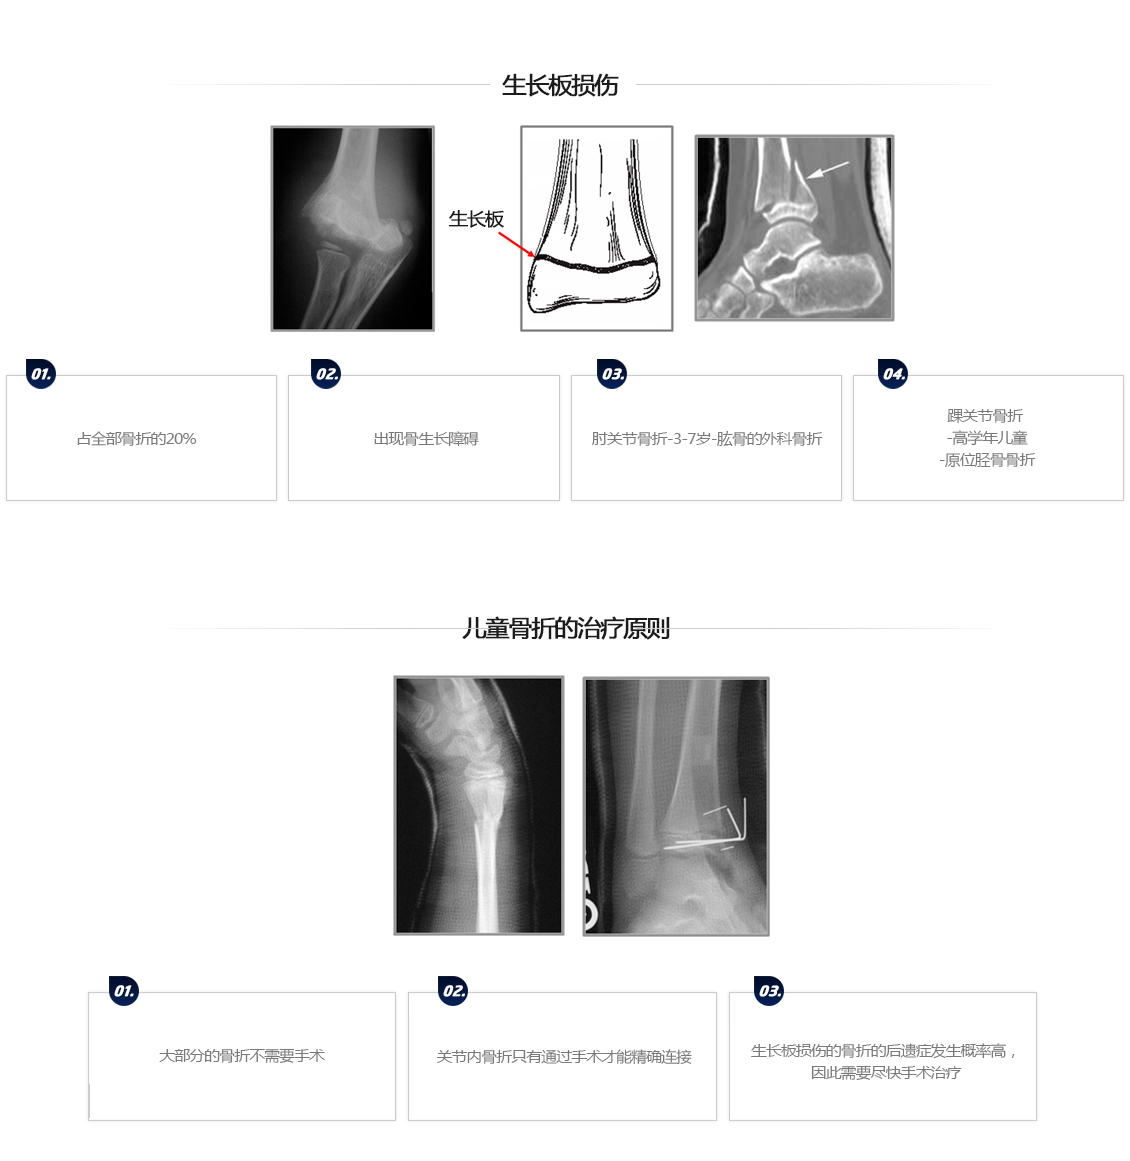

儿科骨折